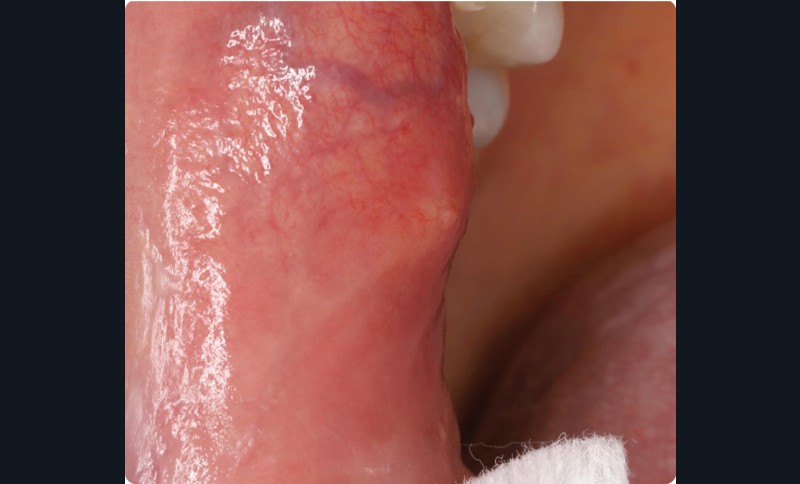

• La lésion siégeait dans la région rétro-commissurale droite, à 1 cm de la commissure, un peu au-dessus de la ligne occlusale. La mise sous tension de la muqueuse faisait apparaître, au centre de la plage érythémateuse, une petite zone jaunâtre. À la palpation, on percevait un nodule ferme, peu mobile, de 2 mm de diamètre environ.